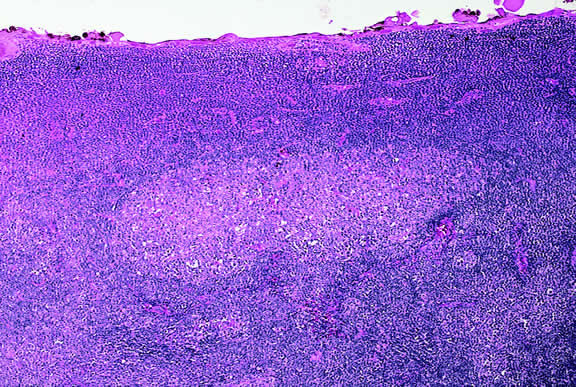

Lymphoma

Although non-Hodgkin's lymphoma often affects the orbit and conjunctiva, intraocular involvement by lymphoma is relatively rare and occurs in two basic ways. First, patients who have widely disseminated systemic lymphoma may develop secondary ocular involvement whose typical manifestation is uveal infiltration. Second, in the variant of central nervous system (CNS) lymphoma that has been called primary lymphoma of the CNS and retina, the vitreous characteristically is involved and the uvea is spared. The latter entity also has been called vitreous large cell lymphoma or ocular “reticulum cell sarcoma.”205–208 In addition to the vitreous, the lymphoma cells also infiltrate the retina, and typically collect between Bruch's membrane and the retinal pigment epithelium, forming solid yellowish RPE detachments, which are highly suggestive of the diagnosis. This rare variant of primary CNS lymphoma should be suspected in older patients who have chronic vitritis that is unresponsive to therapy. Cytologic examination of diagnostic vitrectomy specimens reveals a highly cellular and extensively necrotic infiltrate that contains atypical lymphocytes with prominent nucleoli and protrusions of the nuclear membrane (Fig. 53). The significance of elevated vitreous interleukin 10 levels as a diagnostic marker for lymphoma is controversial.209,210

Fig. 53. Primary central nervous system lymphoma, vitreous. Diagnostic vitrectomy specimen contains large atypical lymphocytes, necrotic lymphoid cells, and nuclear debris. Lymphoma cells in inset have nuclear membrane protrusions and prominent nucleoli. Main figure, Millipore filter. (Hematoxylin-eosin, × 250.)